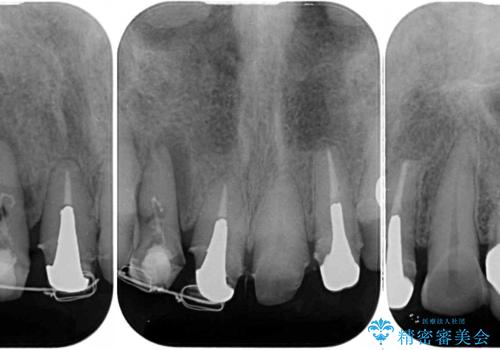

骨格的に下顎骨が前方にあり、歯列の幅も下顎の方が大きいため、奥歯に負担のかかりやすい咬合でした。

大臼歯部は、上下左右ともに咬合により問題が生じており、骨格的な問題から積極的な治療をするべきか判断の難しい状況でした。

臼歯部は痛みが生じている歯に絞って処置を行い、それ以外については手を加えず、現状維持を心がけることとしました。

前歯部については抜歯が必要な歯を抜歯し、インプラントやブリッジなどにより補綴治療を行うこととしました。